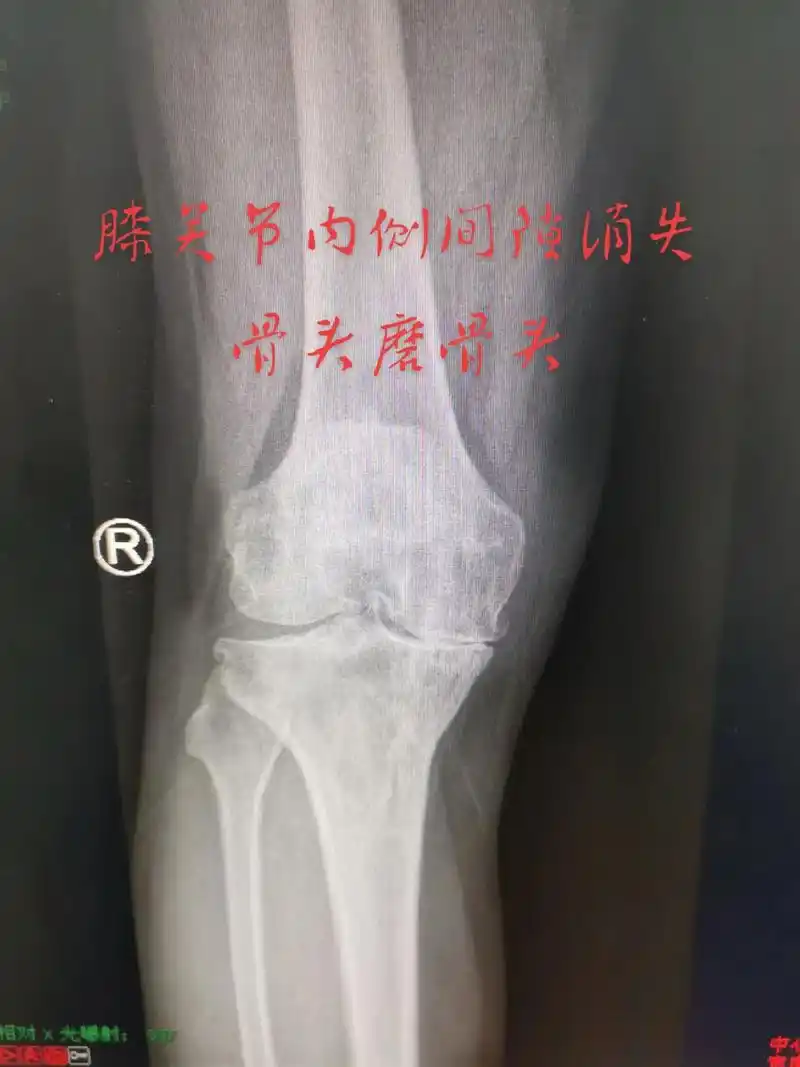

第一张图片是前内侧骨关节炎骨磨骨阶段,如果膝关节疼痛,拍x线 - 抖音